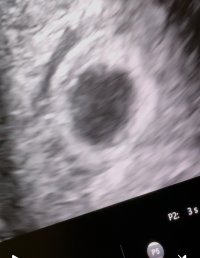

Ble dessverre satt tilbake fra 6+5 til 6+0, noe som er litt rart med tanke på stabil syklus, men da tok det vel litt tid fra EL til befruktning.